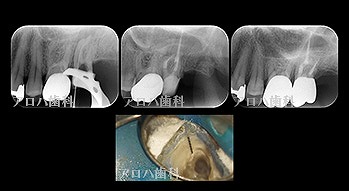

case10

左上に腫脹、圧痛。

根尖部に透過像

術前、術直後、予後

術前、術後